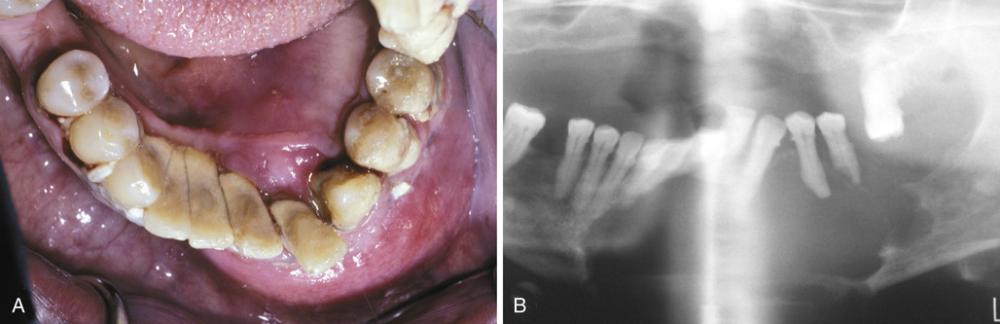

Clinical Features

- develops on buccal of mandibular first or second molar

- occurs in children from 5 to 13 years of age

- slight-to-moderate tenderness

- swelling and foul-tasting discharge

- pocket formation on the buccal aspect

Radiographic Features

- well-circumscribed unilocular radiolucency

- involves buccal bifurcation and root area

- average size is 1.2 cm, but may be up to 2.5 cm

- root apices tipped toward lingual mandibular cortex

Well-circumscribed unilocular radiolucency superimposed on the roots of the mandibular first permanent molar. Periodontal probing revealed pocket formation on the buccal aspect.

buccal bifurcation cyst